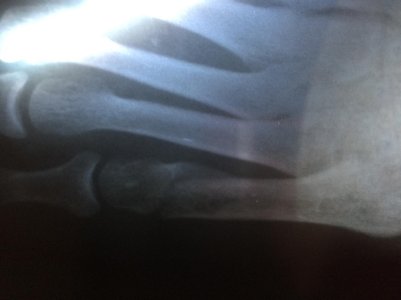

Здравствуйте, мне 19. Рост 150см вес 49, 2 недели назад играла фрисби и повернула ногу, думала ничего серьезного врач приходила сказала связки, спустя 1,5 недели пошла в больницу где мне сделали рентген и написали, что у меня перелом 5-ой плюсневой кости (это написано на польском перевела через переводчик), поставили гипс, сказали через недельку в другую больницу съездить. Сегодня друг забрал мой рентген, посмотрите пожалуйста, ничего серьезного, долго мне придется носить гипс, так как через 5 дней у меня поездка, можно мне ходить? иногда наступаю дома на ногу мне не больно ходить еще. Посмотреть вложение 12228